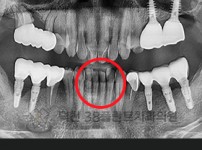

치료전후